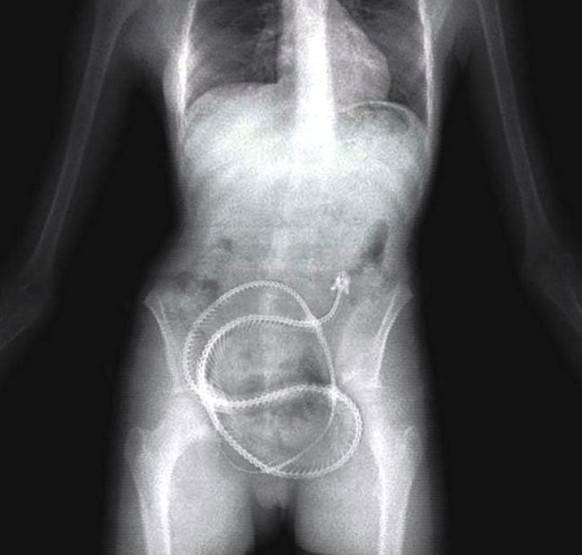

La souris est plus spectaculaire que le serpent.